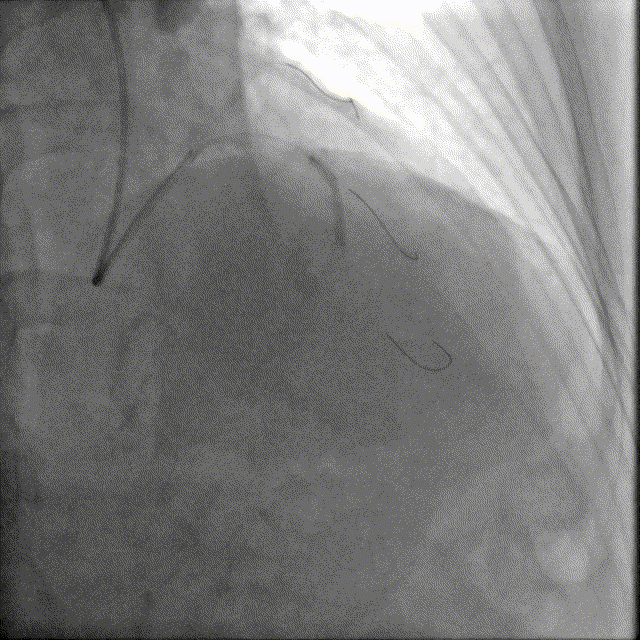

于前降支中段近段口串联2.5mm×18mm、3.0mm×18mm DES。

前降支开口精确定位植入3.5mm×18mm DES。

2.5mm-3.5mm后扩球囊后扩张。

最终结果满意,复查IVUS支架膨胀、贴壁良好!